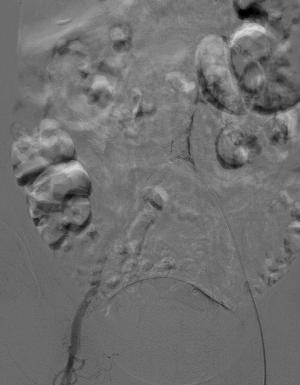

Numed18球囊扩张